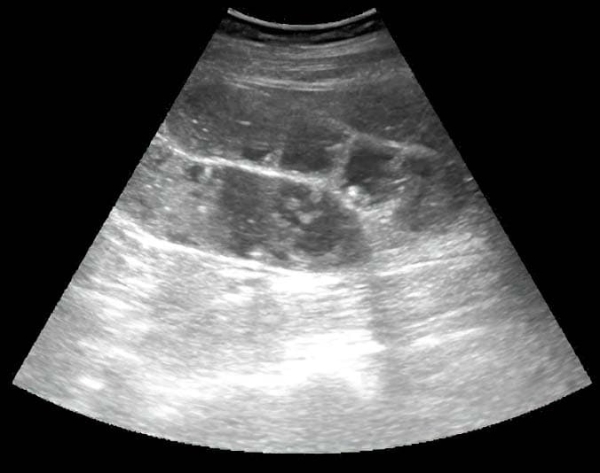

Рисунок 9. Картина УЗИ при гангренозном аппендиците.Из протокола УЗИ: «В правой подвздошной области визуализируется слепо заканчивающийся, не перистальтирующий участок кишки 10 мм в диаметре, болезненный при компрессии датчиком; в просвете жидкость и каловые камни» (см. рис. 9).

Из протокола операции: «Аппендикс резко утолщен, напряжен, грязно-серого цвета, покрыт фибрином». Диагноз после операции: гангренозный аппендицит (см. рис. 10).